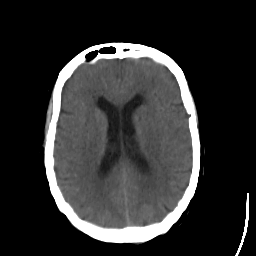

Stroke CT #1 -- Slice #15

[Home][Help][Clinical] Slice 15